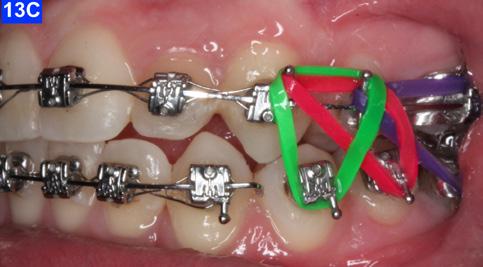

Finally, after 21 months of treatment, the patient and the parents consented to the odontectomy of the maxillary first bicuspids. The informed consent forms for the extractions and placement of TADs were signed by the parent, and all questions were answered. Risks, benefits, alternatives, and the result of no treatment at all were reviewed. Immediately after the odontectomy of #14(5) and #24(12), 1.6 x 8.0 mm AnchorPro (OrthoOrganizers) TADs were placed just mesially to the maxillary second bicuspids.6 In office power arms (a .018 x.025 SS) were fabricated and bonded to the buccal surface of the maxillary cuspids, just above the bracket.7 The purpose of the power arm is to place the applied force as close to the center of resistance of the tooth as possible. In this manner the line of action (power hook to the TAD) is parallel to the occlusal plane. The source of the force is an EC, and it must be replaced at least bi-weekly. Both arches had a .018 SS arch wire. There was a small off-center bend (tip-back, gable bend) “V” pointing occlusally, mesial to the maxillary second bicuspids.8 The purpose of this bend is to keep the roots parallel during the translation of the cuspids. There was a small OCS between #21(9) and #23(11) to shift the maxillary midline to the right. Another OCS was placed between #32(23) and #34(21) to facilitate the alignment of the mandibular left cuspid (Figure 8-A, B, C, D).

To prevent a disto-lingual moment (rotation) of the maxillary cuspids we attached PC from the lingual button on the cuspids to the framework on the hyrax. The anterior portion of the Hyrax was cut off and the remaining portion served as a TP arch for posterior anchorage. At this point, we were 25 months into treatment (Figure 9-A, B, C, D). The hyrax was removed after 30 months of treatment.